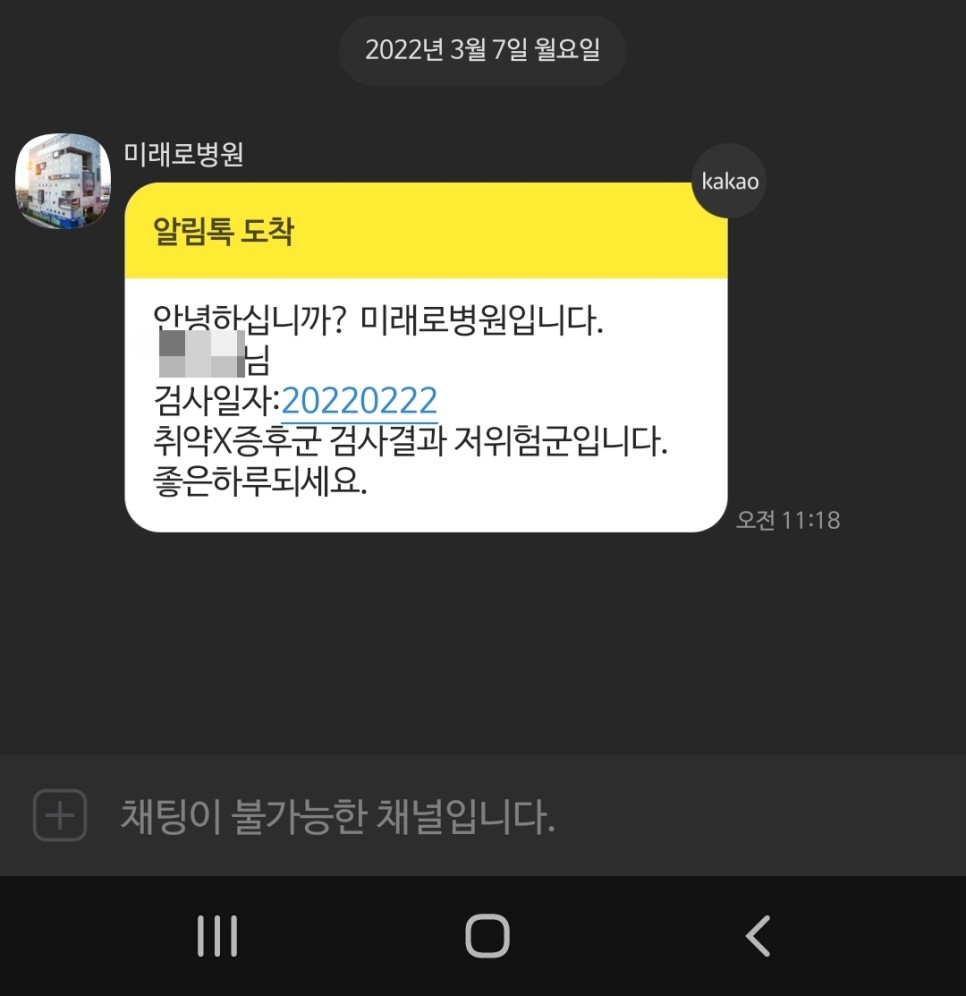

2주 후 검사 결과 통보 기형아 검사와 마찬가지로 검사 결과는 1주일 후 문자로 간다고 하셨으나 2주가 지나도록 연락이 없어 미래로 병원에 전화를 드렸습니다. 전화했더니 저 위험군이라고 알려줬어요. 결과 통지를 잊어버린 것 같아요. ㅎㅎ 그리고 안내문자로도 보내준다고 해서 검사결과 ‘저위험군’이라는 알림이 왔습니다.